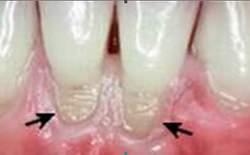

Cổ răng cửa và răng hàm có thể bị mòn thành khía rãnh có hình chữ V ở mặt ngoài và gây nên ê buốt và có thể tiến triển gây viêm tủy răng. Nguyên nhân thường là do chải răng không đúng phương pháp.